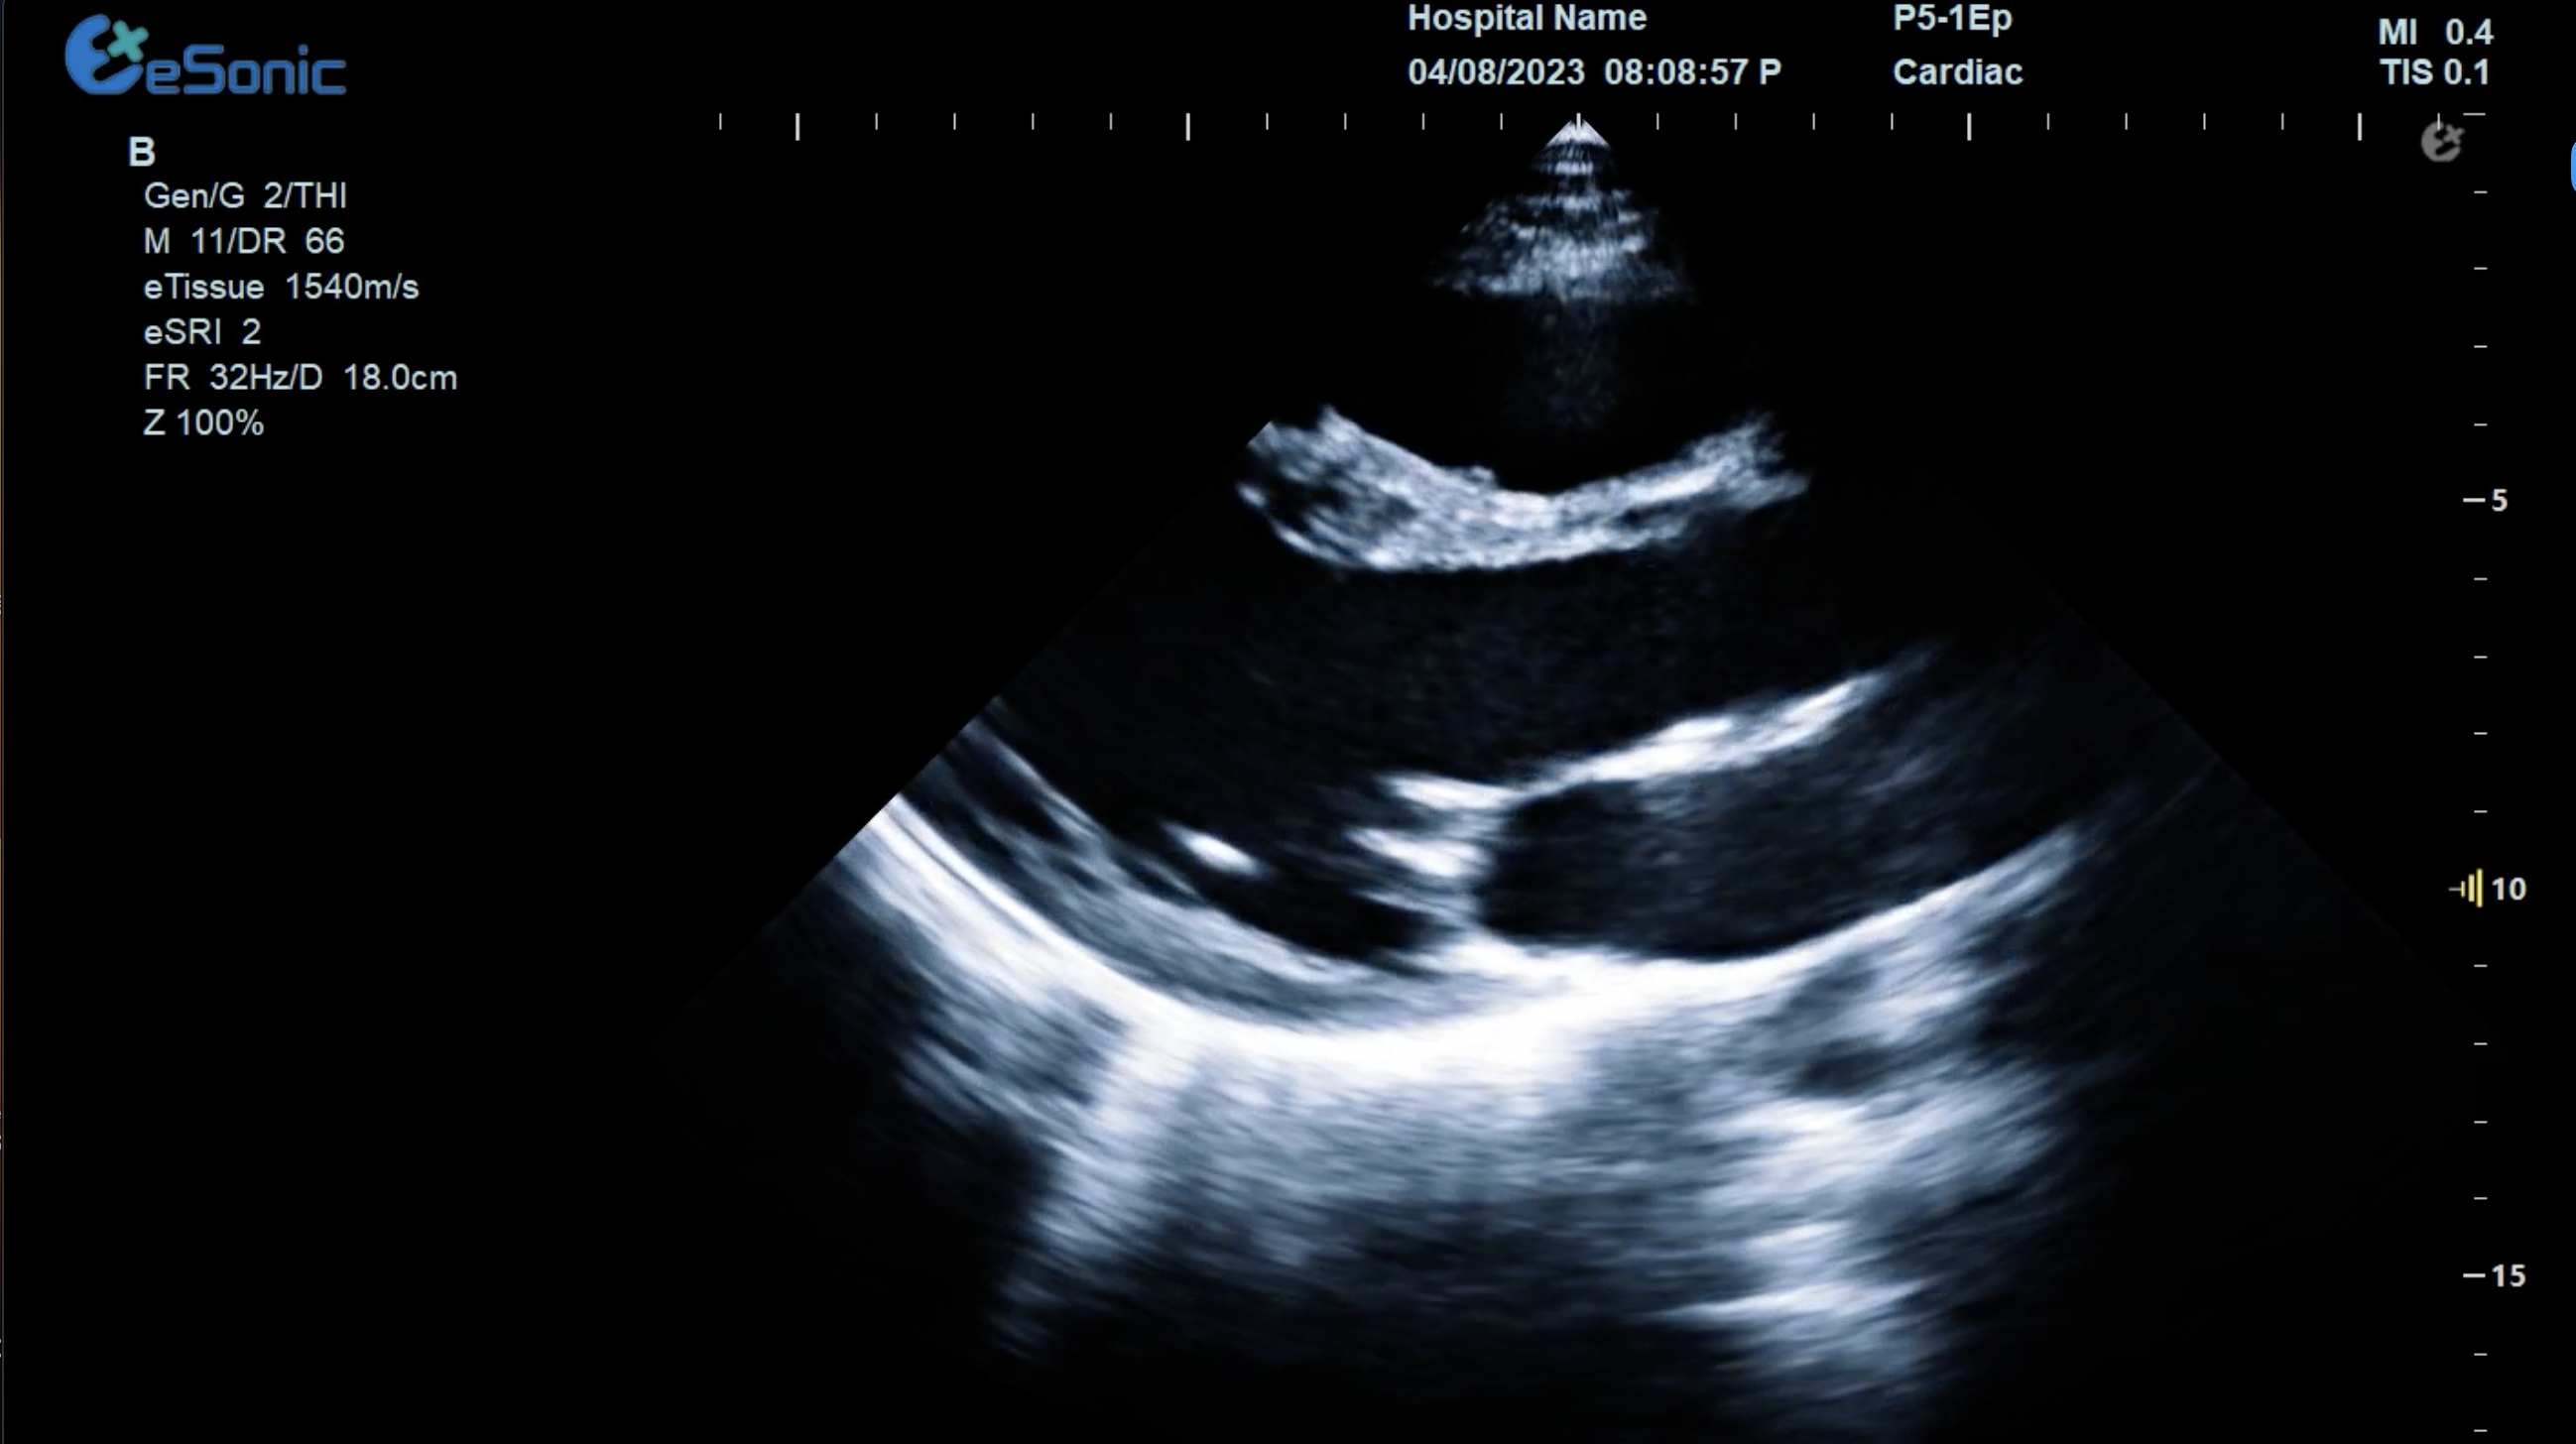

女性,68岁,临床诊断:冠心病

超声表现:左房大,左室壁运动幅度明显减低,以室间隔较明显;心包腔内见无回声区,右室前壁8mm,左室侧壁10mm。

冠心病、心包积液